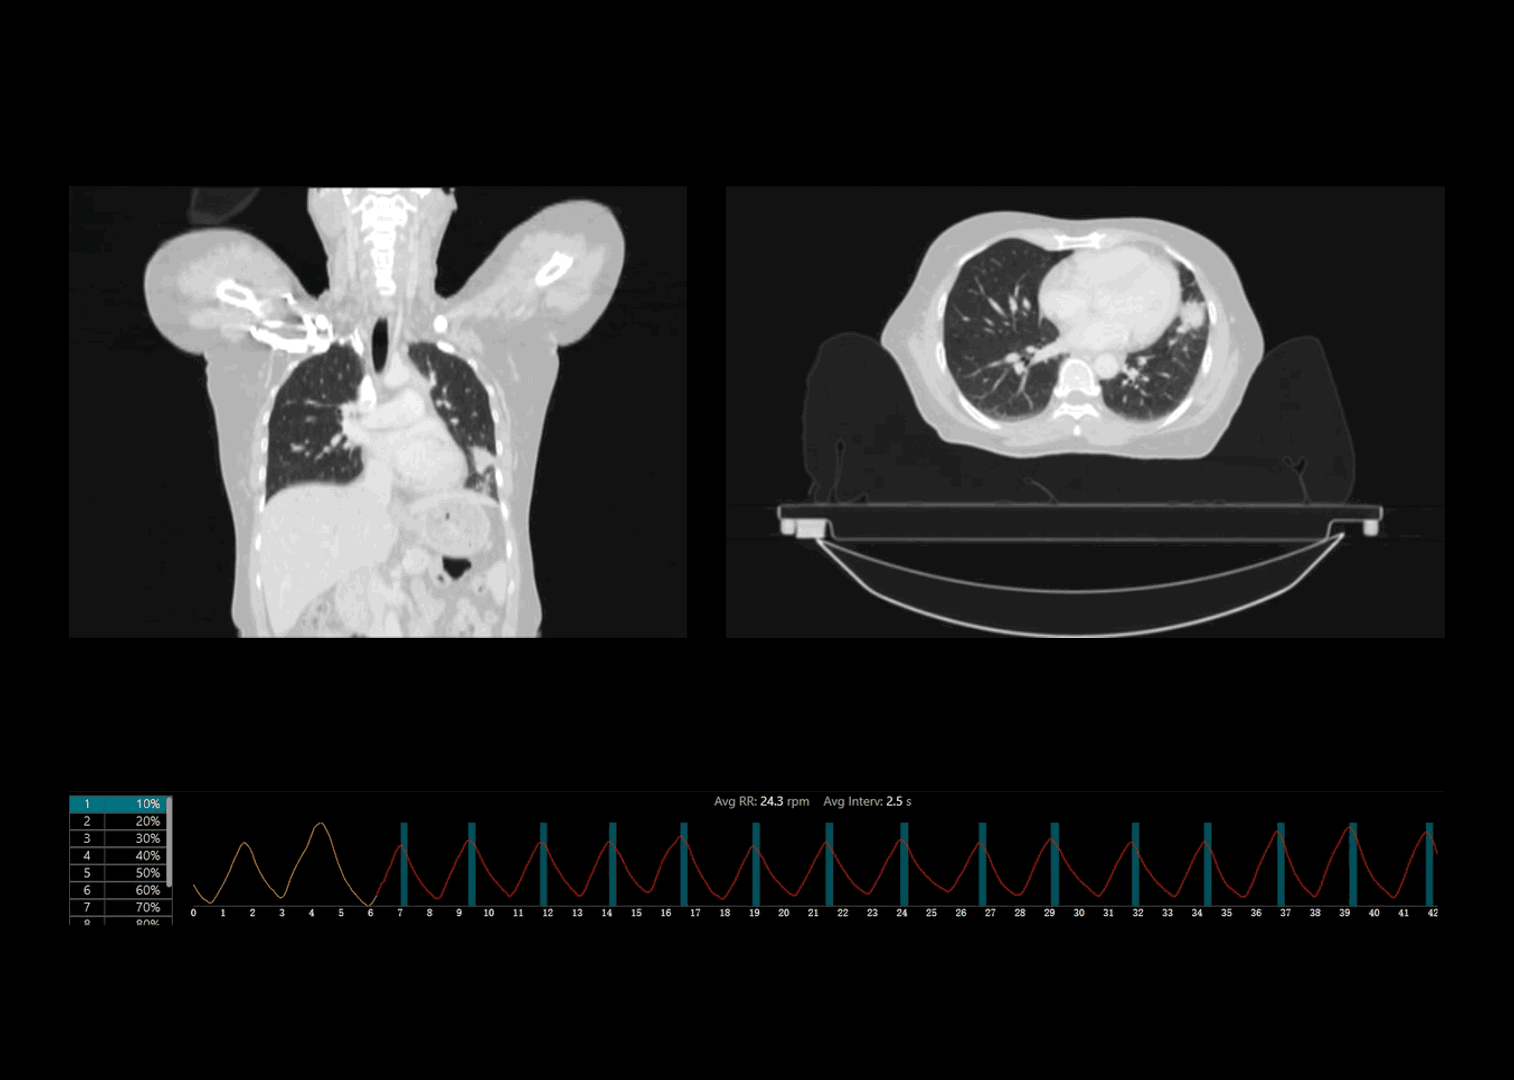

运动器官动态追踪

多种扫描模式

支持前瞻式断层扫描、前瞻式螺旋扫描和回顾式螺旋扫描,应对各类放疗应用场景

呼吸信号精准探测

联影自研压力传感式呼吸门控系统精准记录规律呼吸、咳嗽异常等各类临床场景下的呼吸信号

自适应螺距采集

基于实际呼吸频率情况自适应推荐最佳螺距参数,相较于传统固定螺距采集,有效减少图像运动伪影

更宽采集范围覆盖

超快机架转速结合球管超长连续曝光能力,采集范围相较传统大孔径CT系统提升2倍*,覆盖各类临床应用场景

*相较于0.5秒/360°转速、120秒球管最长曝光时间的CT系统

肺部病灶4DCT高清成像